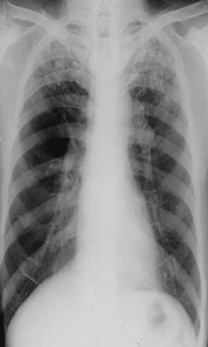

斑片狀陰影位于雙肺尖,根據(jù)公式診斷浸潤性肺結(jié)核